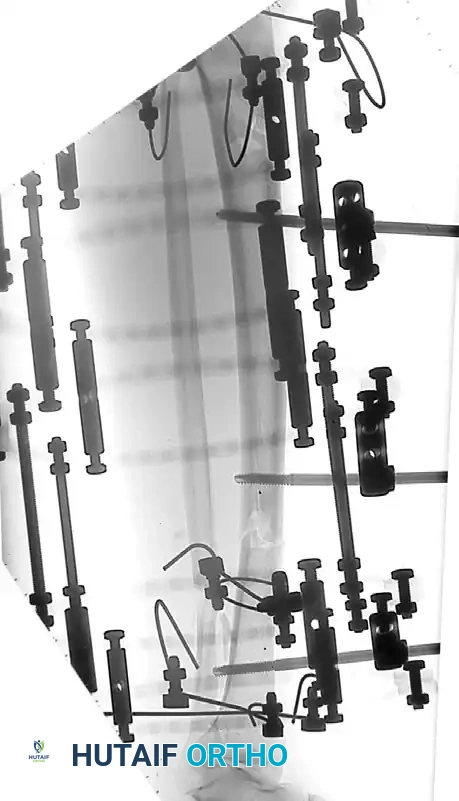

Step-by-Step Surgical Technique

1. Preoperative Planning and Positioning

- Evaluate orthogonal radiographs to determine fracture geometry and plan pin placement. Ensure pins are placed at least 1.5 to 2 cm away from the fracture lines to avoid propagating cracks.

- Position the patient on a radiolucent table. Ensure the C-arm fluoroscope can freely image the entire bone in both AP and lateral planes.

2. Pin Insertion Technique

- Incision: Make a longitudinal stab incision (1-2 cm) through the skin. Do not use a puncture technique, as skin tension around the pin leads to necrosis and infection.

- Blunt Dissection: Use a hemostat to bluntly dissect down to the periosteum. Insert a tissue protection sleeve (drill guide) firmly against the bone.

- Pre-drilling: Always pre-drill the near and far cortices using a sharp drill bit. Use continuous saline irrigation to cool the drill bit. Thermal necrosis from drilling is the primary cause of premature pin loosening and ring sequestrum formation.

- Pin Placement: Insert the half-pin manually or on low speed. Ensure the pin engages the far cortex but does not protrude more than 1-2 threads to avoid tethering far-side soft tissues.

3. Frame Assembly and Reduction

- Apply the pin-to-bar clamps to the pins.

- Attach the longitudinal carbon fiber or titanium rods.

- Perform the fracture reduction under fluoroscopic guidance using manual traction.

- Once length, alignment, and rotation are restored, sequentially tighten all clamps.

- Verify the final reduction and ensure the frame is 2-3 cm away from the skin to accommodate swelling.